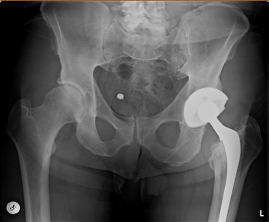

He underwent primary left THA using a Longevity HXLPE liner, Trilogy acetabular cup, VerSys Heritage cemented femoral stem, and a 28-mm CoCr alloy femoral head (Figure 1). The postoperative course was unremarkable after a five-day hospital stay.

- A man in his 40s underwent primary left THA in 2001 with a Triology cup, Longevity HXLPE liner, CoCr femoral head, and VerSys Heritage cemented femoral stem.